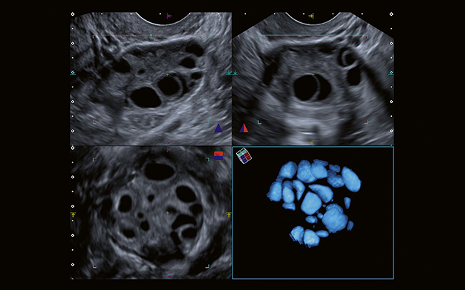

Luminance 3D : propose des images 3D réalistes et haute définition, permettant un aperçu détaillé (Sonde matricielle).

MultiView : offre des coupes transversales en haute résolution, pour mieux visualiser les relations anatomiques et évaluer l’étendue d’une lésion avec précision.